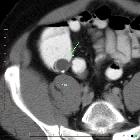

- Mukozele der Appendix

- muzinöse Neoplasien der Appendix

- neuroendokriner Tumor der Appendix

- muzinöses Zystadenokarzinom der Appendix

- Adenokarzinom der Appendix

- Karzinoid der Appendix

- appendiceal adenoma

- appendiceal mucinous adenoma

- appendiceal mucinous cystadenoma

- appendiceal mucinous adenocarcinoma